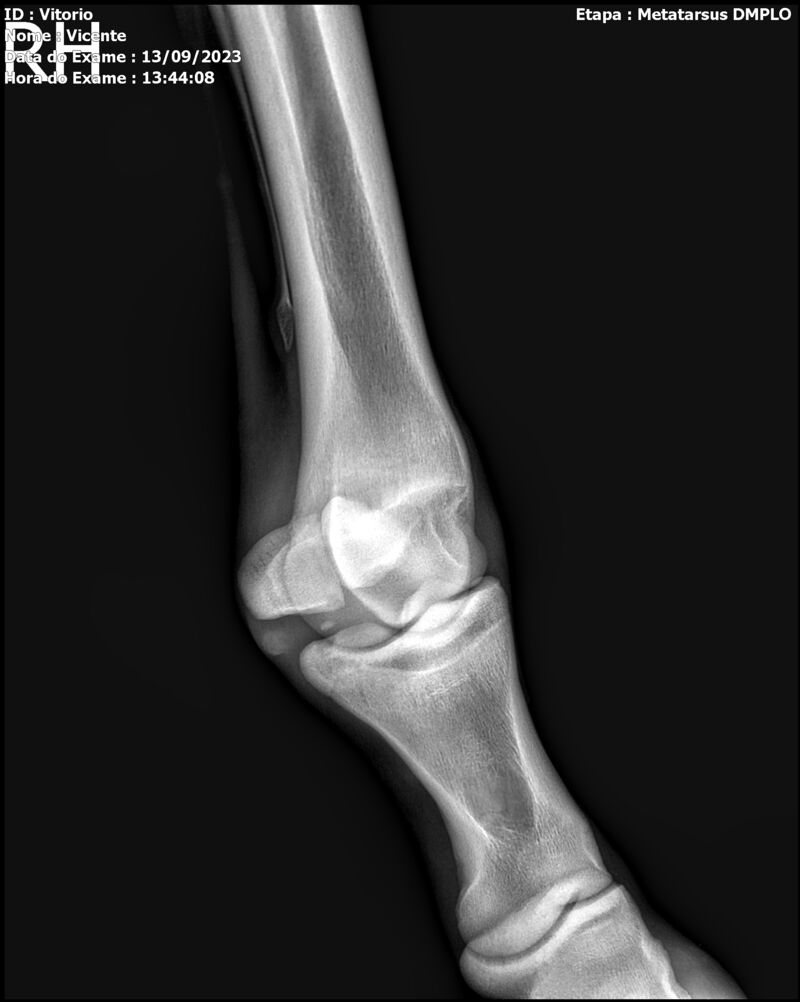

THUNDER ZC

Raça: BRASILEIRO DE HIPISMO

Sexo: MACHO - POTRO

Nascimento: 17/09/2022

Altura Aproximada: 1,54

Pel.: CASTANHO

Registro: EM AND

Vend.: VICENTE CONTE

Local : PORTO FELIZ/SP